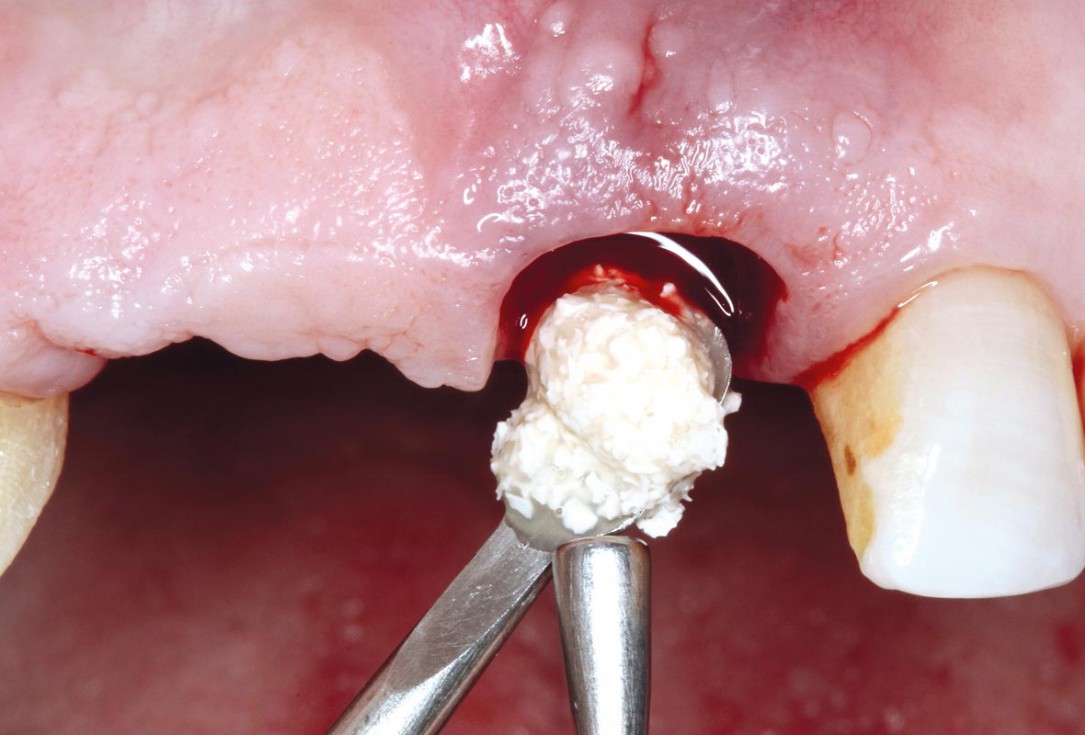

05/17 - Small cerabone® granules.

Socket preservation using cerabone® and Straumann® Emdogain® - Dr. S. Pelekanos